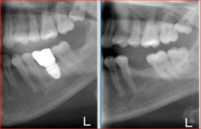

45y.o male initially presented with failing upper dentition due to chronic advanced periodontitis (gum disease).

All upper teeth had been extracted utilizing special surgical techniques for bone preservation and bone grafting. Among those were: Partial Extraction Therapy (PET), Bilateral Sinus Elevation (Sinus Lift).

Seven dental implants had been inserted using Digital Guided Placement Method. The surgical phase had been finalized with soft tissue grafting to insure proper gum seal around dental implants for long term success and to prevent peri-implantitis.

After completion of bone integration (healing) The final prosthetic phase had been accomplished with fabrication of the full contour zirconia non-removable (fixed) bridge.

This patient presented with the poor prognosis for his upper teeth, severe bone loss and bite problems.

After thorough evaluation Dr. Andrews recommended ALL-ON-6 fixed implant bridge. The entire surgical stage, including extractions of all remaining upper teeth, bi-lateral sinus lift (right and left side), multiple bone grafts and placement of all 6 dental implants was accomplished by Dr. Andrews in one visit. Six months later the full upper arch dental implant bridge was delivered.